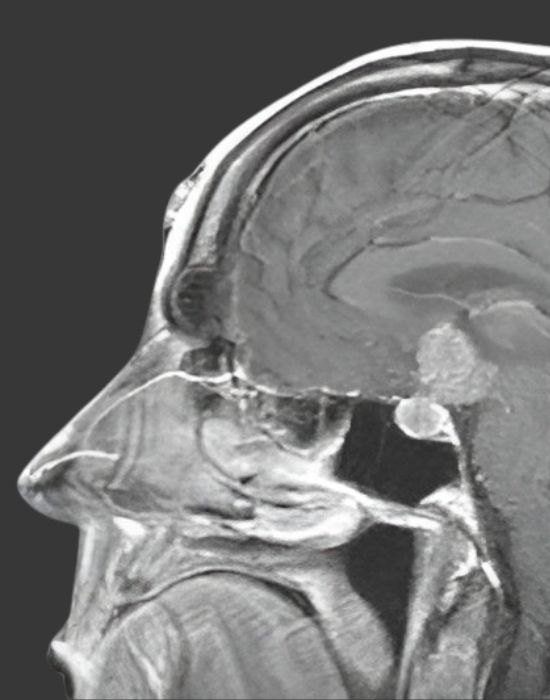

МРТ і КТ головного мозку: укладка, протоколи, артефакти — все, що потрібно в роботі